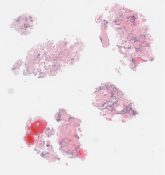

CANP2008-1.svs

60000 x 37785

@ 20X